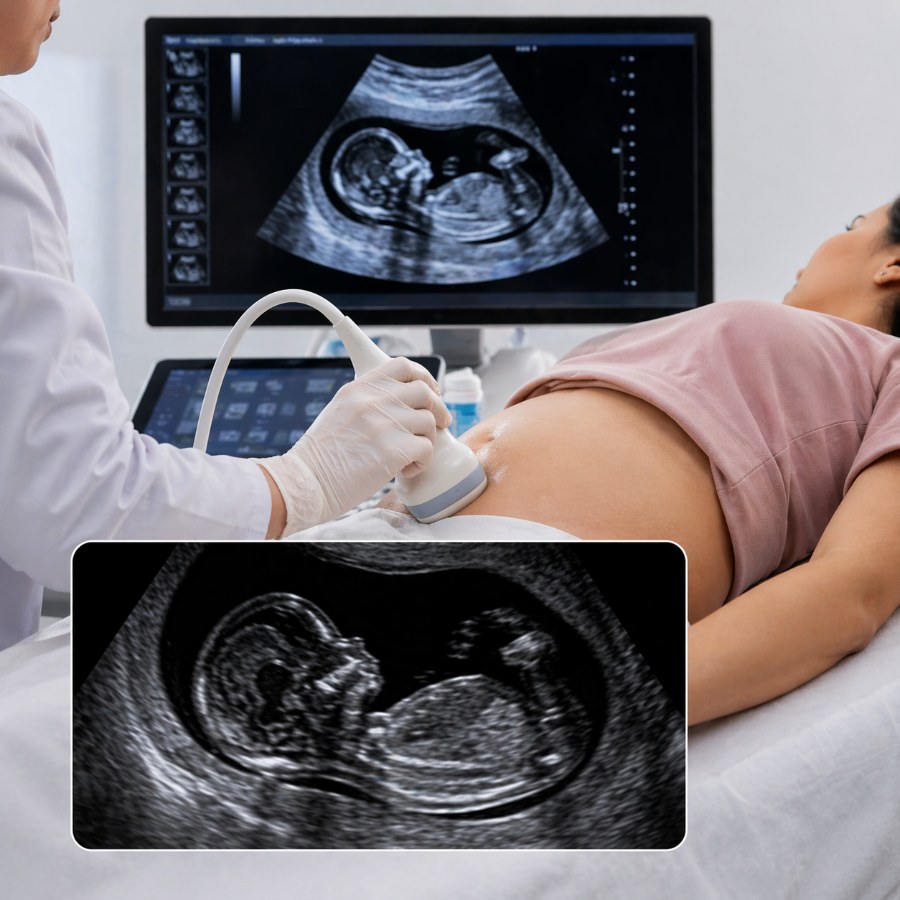

An NT NB Scan is an important pregnancy ultrasound performed during the first trimester to assess the baby’s early development and screen for chromosomal abnormalities. It includes:

• NT (Nuchal Translucency) – measures fluid behind the baby’s neck

• NB (Nasal Bone) – checks the presence and development of the baby’s nasal bone

This scan helps identify the risk of conditions such as Down syndrome and other fetal abnormalities.

The NT NB Scan is usually performed between 11 weeks and 13 weeks 6 days of pregnancy. It is a safe ultrasound test that helps evaluate fetal growth and early markers for genetic conditions.